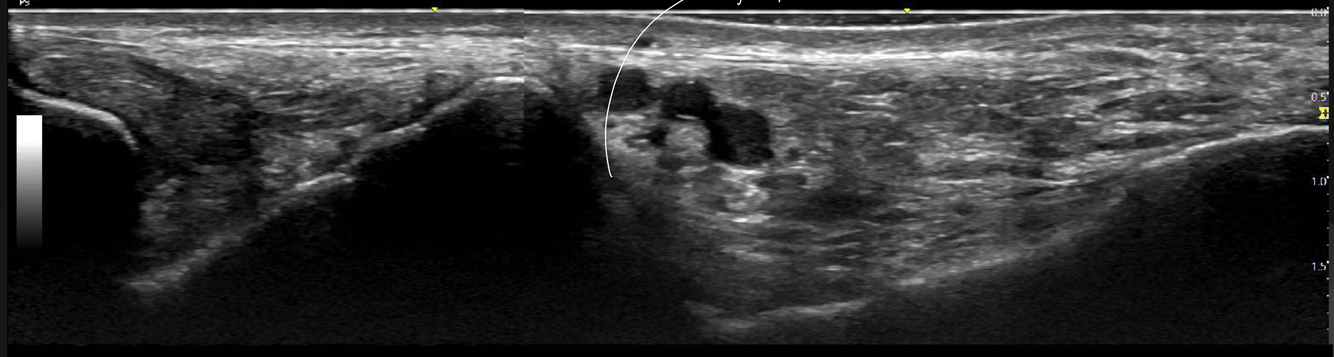

Identifier les structures sur cette image.

Indice: On y voit les os suivants : Tibia, talus et calcanéus

A